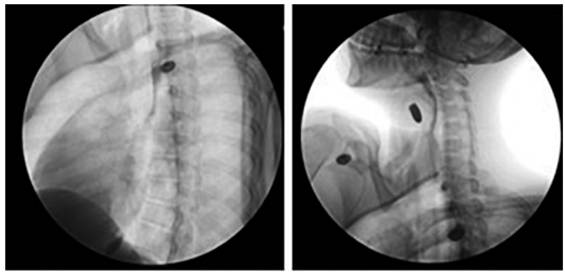

Ante la sospecha clínica de lesión vascular cervical como primera posibilidad, se tomó una radiografía de tórax postero-lateral que descartó la presencia de neumotórax, hemotórax u otra complicación (figura 3). Se realizó un angiotac cervical con contraste endovenoso, encontrando enfisema subcutáneo en los tejidos blandos, con solución de continuidad (figura 4) y una lesión en el tercio medio de la tráquea, con compromiso de su pared lateral derecha (figura 5), sin poder descartar una lesión del esófago en su segmento cervical. No se observó compromiso vascular ni óseo.